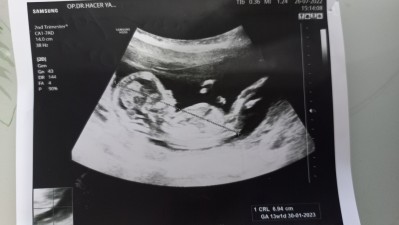

Sizce bebegimin cinsiyeti ne ? Tahmin edebilen anneler

Cinsiyet tahmini yapabilirmisiniz

13+2

Benim yarın kontrölum var canım 13+2 olucaz söyler diye düşünuyordum sana söylemedimi cinsiyeti bu arada erkege benzetdim hayırlısı

Bacakları kapalı dedi doktor bir türlü göstermedi 3 hafta sonra tekrar gitmemi söyledi bakalım hayırlısı insanlah sen öğrenirsin

Bende erkege benzetdim sağ salim.kucaginza alın bebeklerinizi

erkeğe benziyor. Allah sağlıkla kucağınıza almayı nasip etsin.

Ben Kıza çok benzettim hayırlısı olsun tabi

Erkege benziyor canmm sen ne bekliyordun inş umdugunu rabbbimm gonlune verir saglikli shatli sekilde